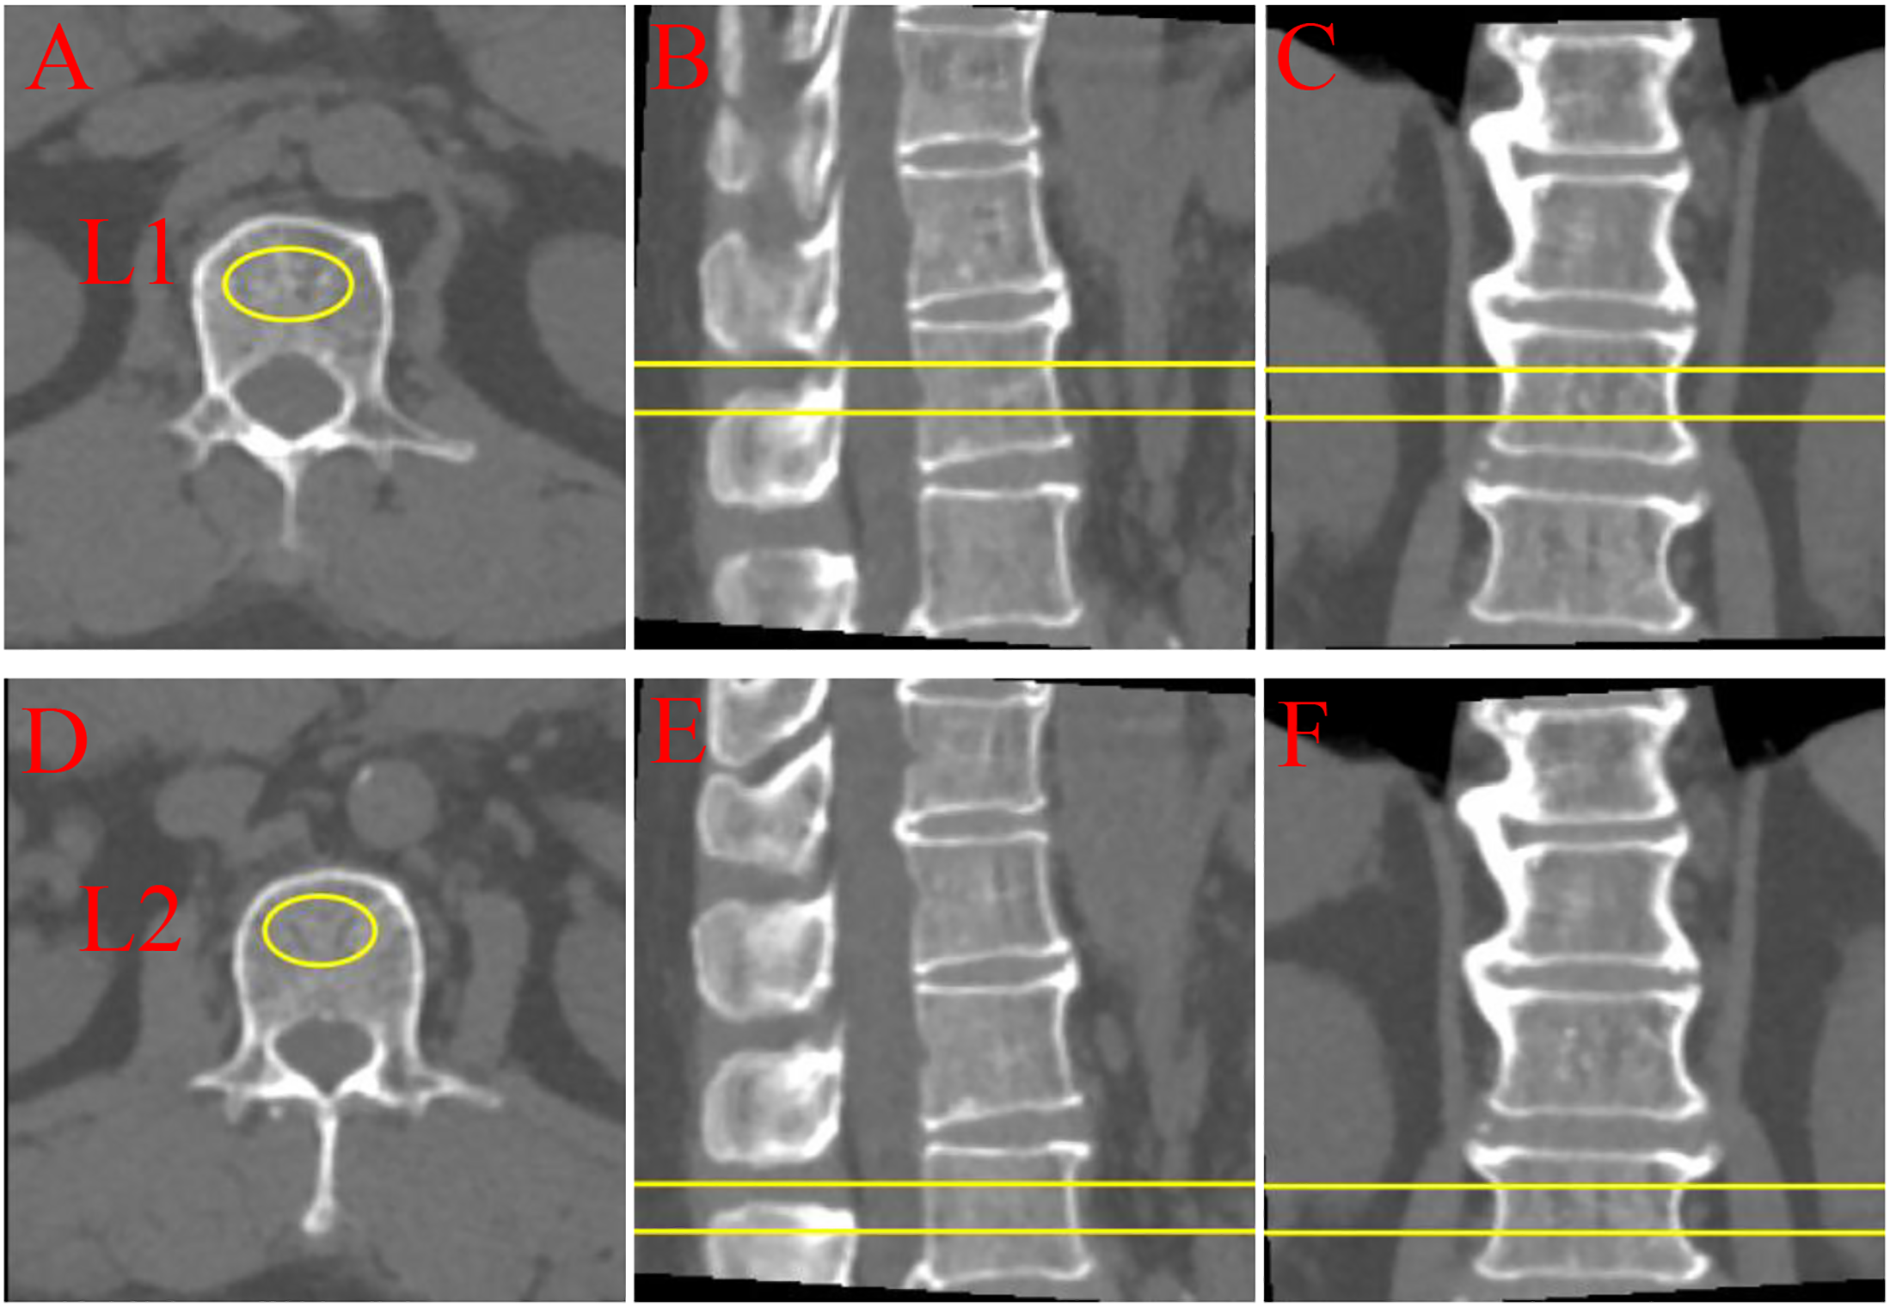

Further analysis of the lumbar BMD of all participants was conducted based on low-dose chest CT during scans to avoid additional radiation exposure. Unified CT scan parameters were used for all participants, and volumetric BMD measurement was performed using Mindways Quantitative Computed Tomography (QCT) Pro 6.1 (Mindways Software, Inc., Austin, TX, USA). The volumetric BMD by QCT is more sensitive to changes in BMD than the areal BMD via dual-energy x-ray absorptiometry (23). Specifically, QCT Pro 6.1 analysis (Mindways Software, Inc., Austin, USA) was used to assess the trabecular volumetric BMD (mg/cm³) of the lumbar spine (L1–L2). Trained professional radiologists measured each vertebra thrice using QCT software and obtained the average of the three measurements as the final BMD for each vertebra. As illustrated in Figure 2. The scientific validity of this method has been confirmed by previously published studies (24).

Figure 2

Quantitative computed tomography (QCT) multi-planar imaging of lumbar vertebrae L1 and L2. (A-C) L1 vertebra: (A) Axial, (B) sagittal, and (C) coronal views; (D-F) L2 vertebra: (D) axial, (E) sagittal, and (F) coronal views. Yellow markers and lines indicate regions of interest and measurement planes. QCT provides three-dimensional bone density assessment through orthogonal imaging planes, enabling comprehensive evaluation of vertebral structural characteristics.